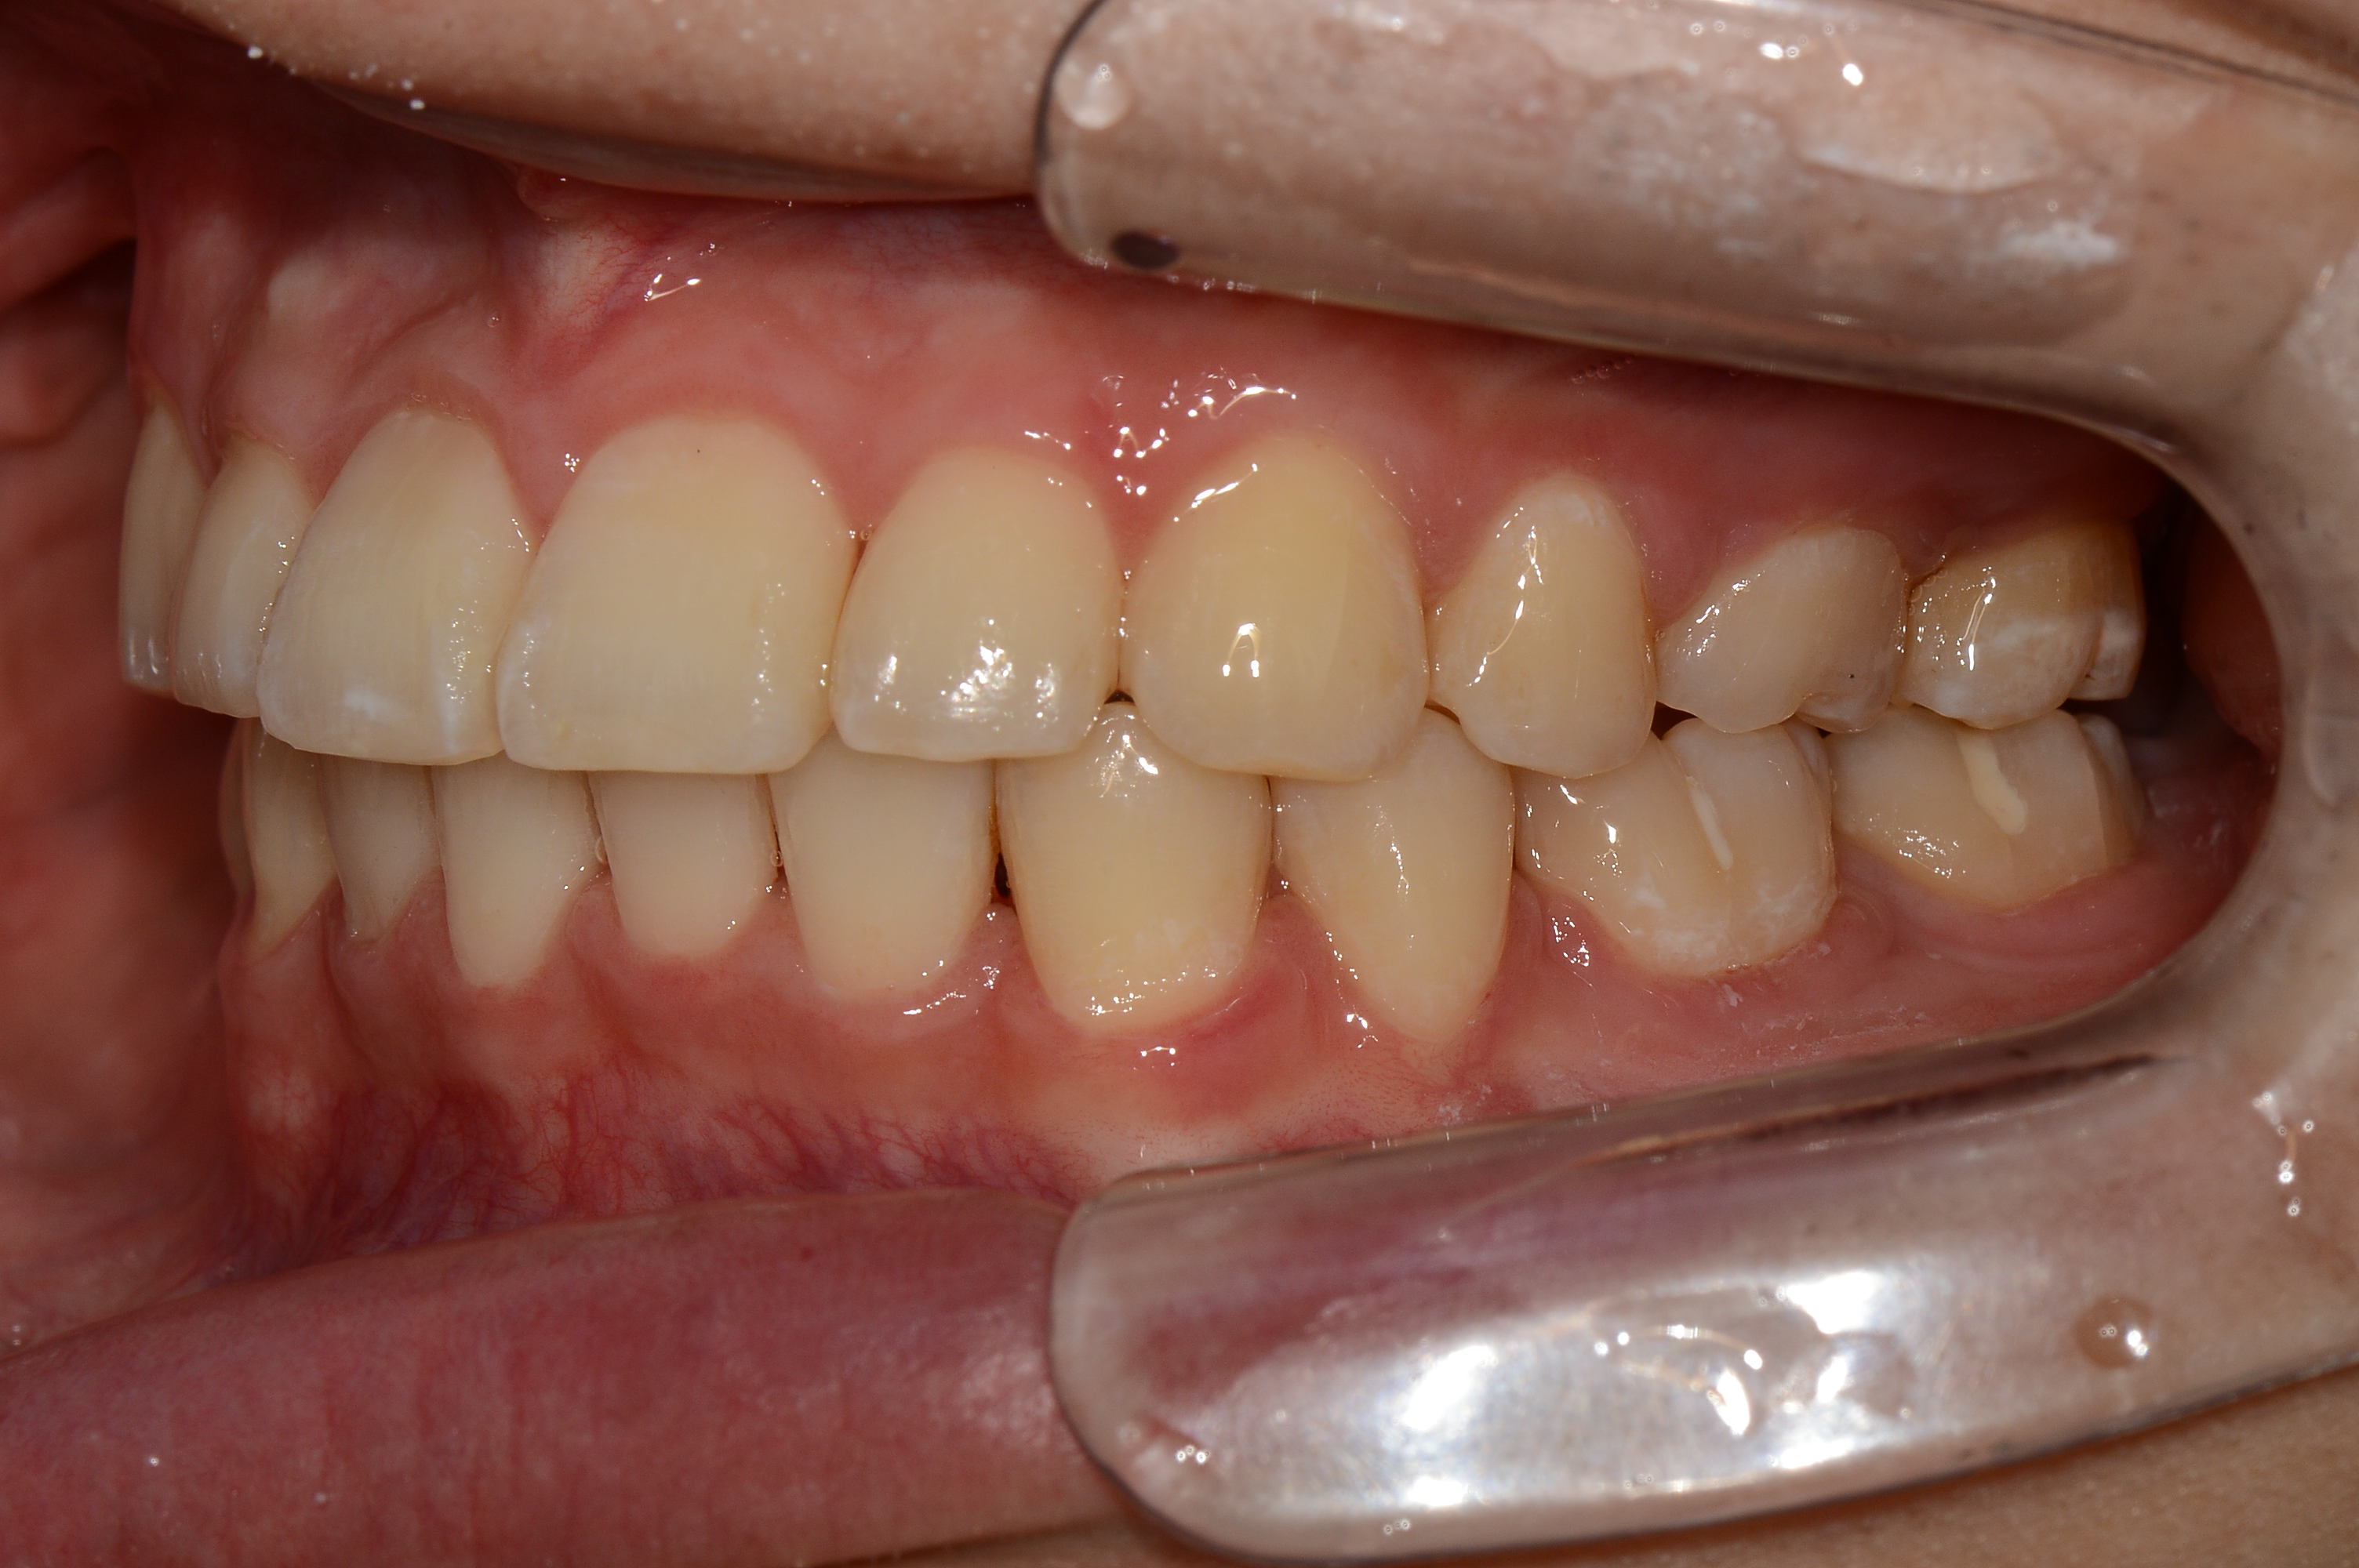

치료 후 사진입니다.